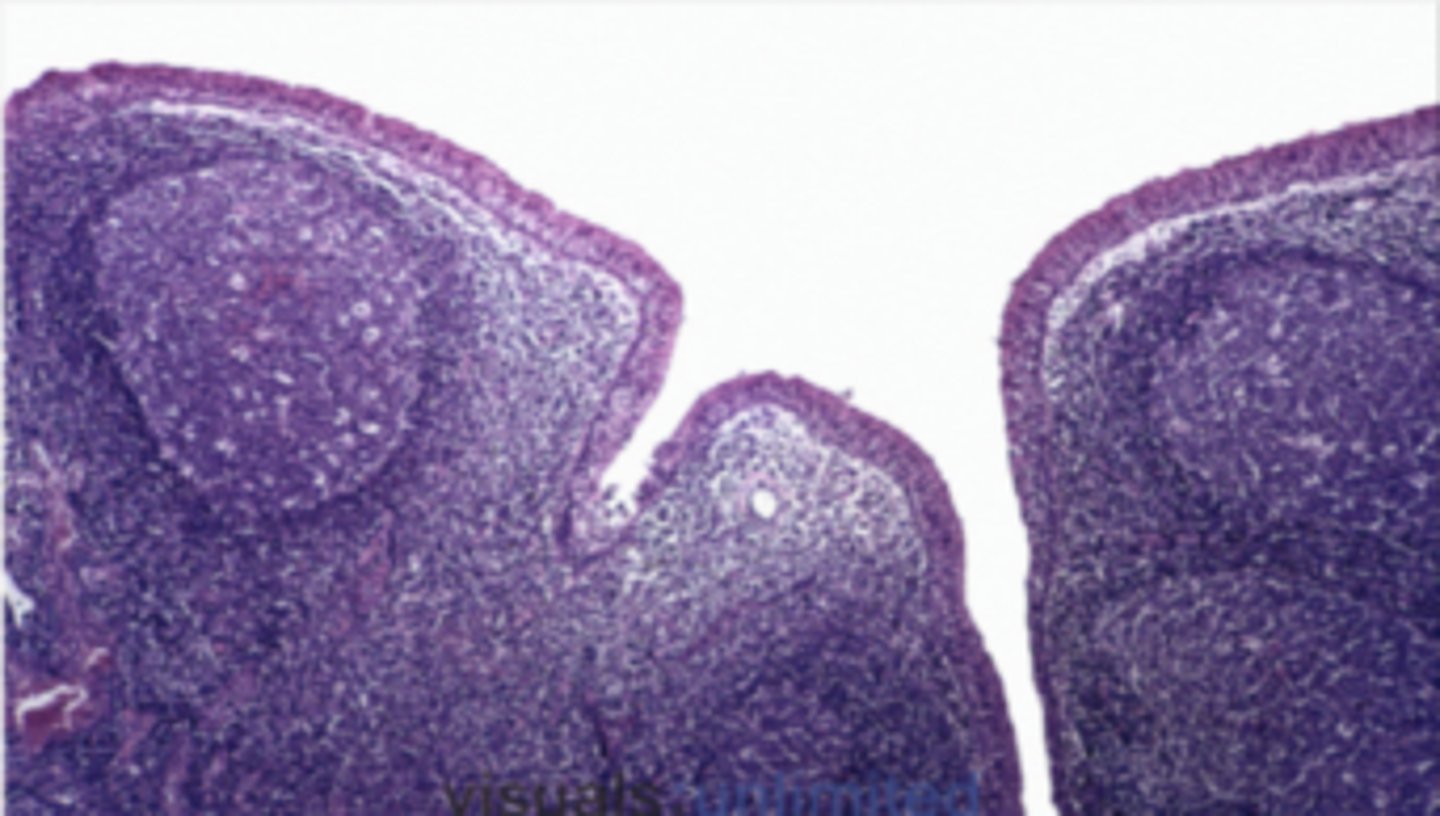

Lymph node

Which of the following organs has a paracortex?

circle around germinal center